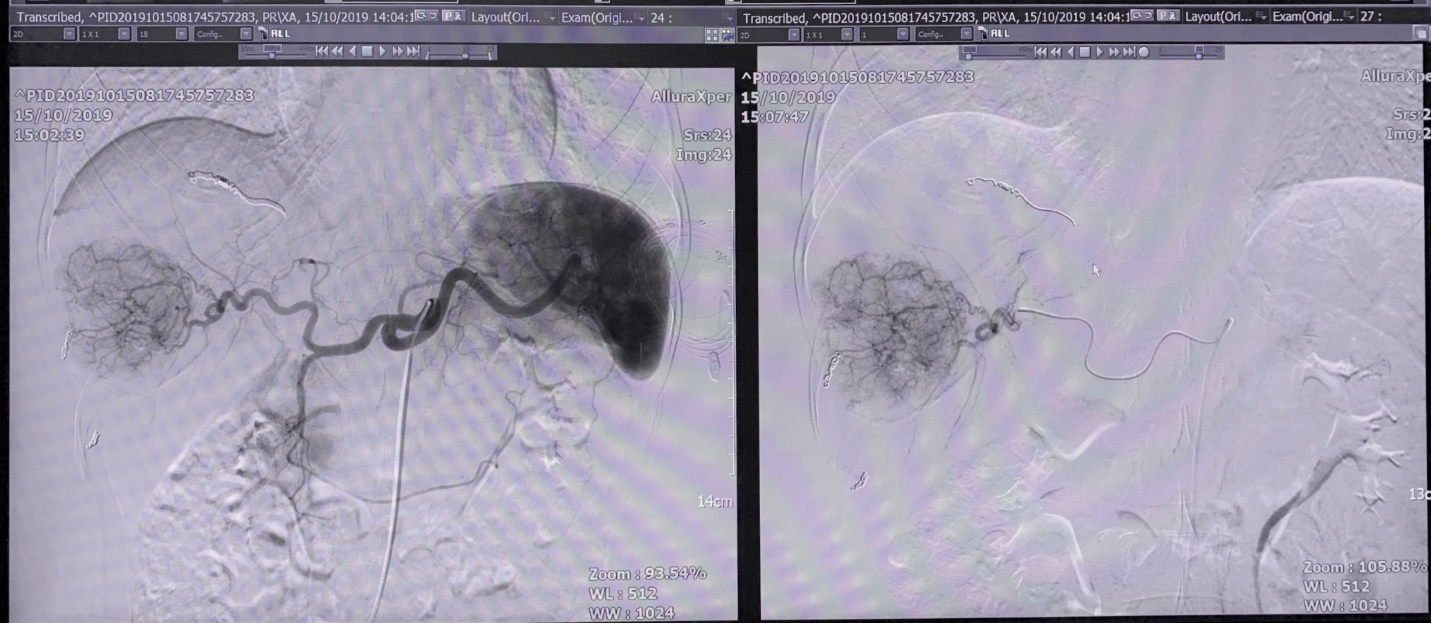

Hình 3: Chụp mạch máu gan, u gan